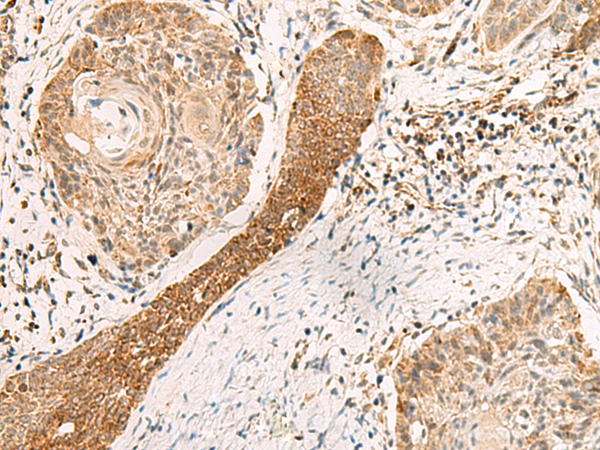

分类: 科研抗体货号: P09904别名: PSP1应用: IHC反应种属: Human, Mouse, Rat